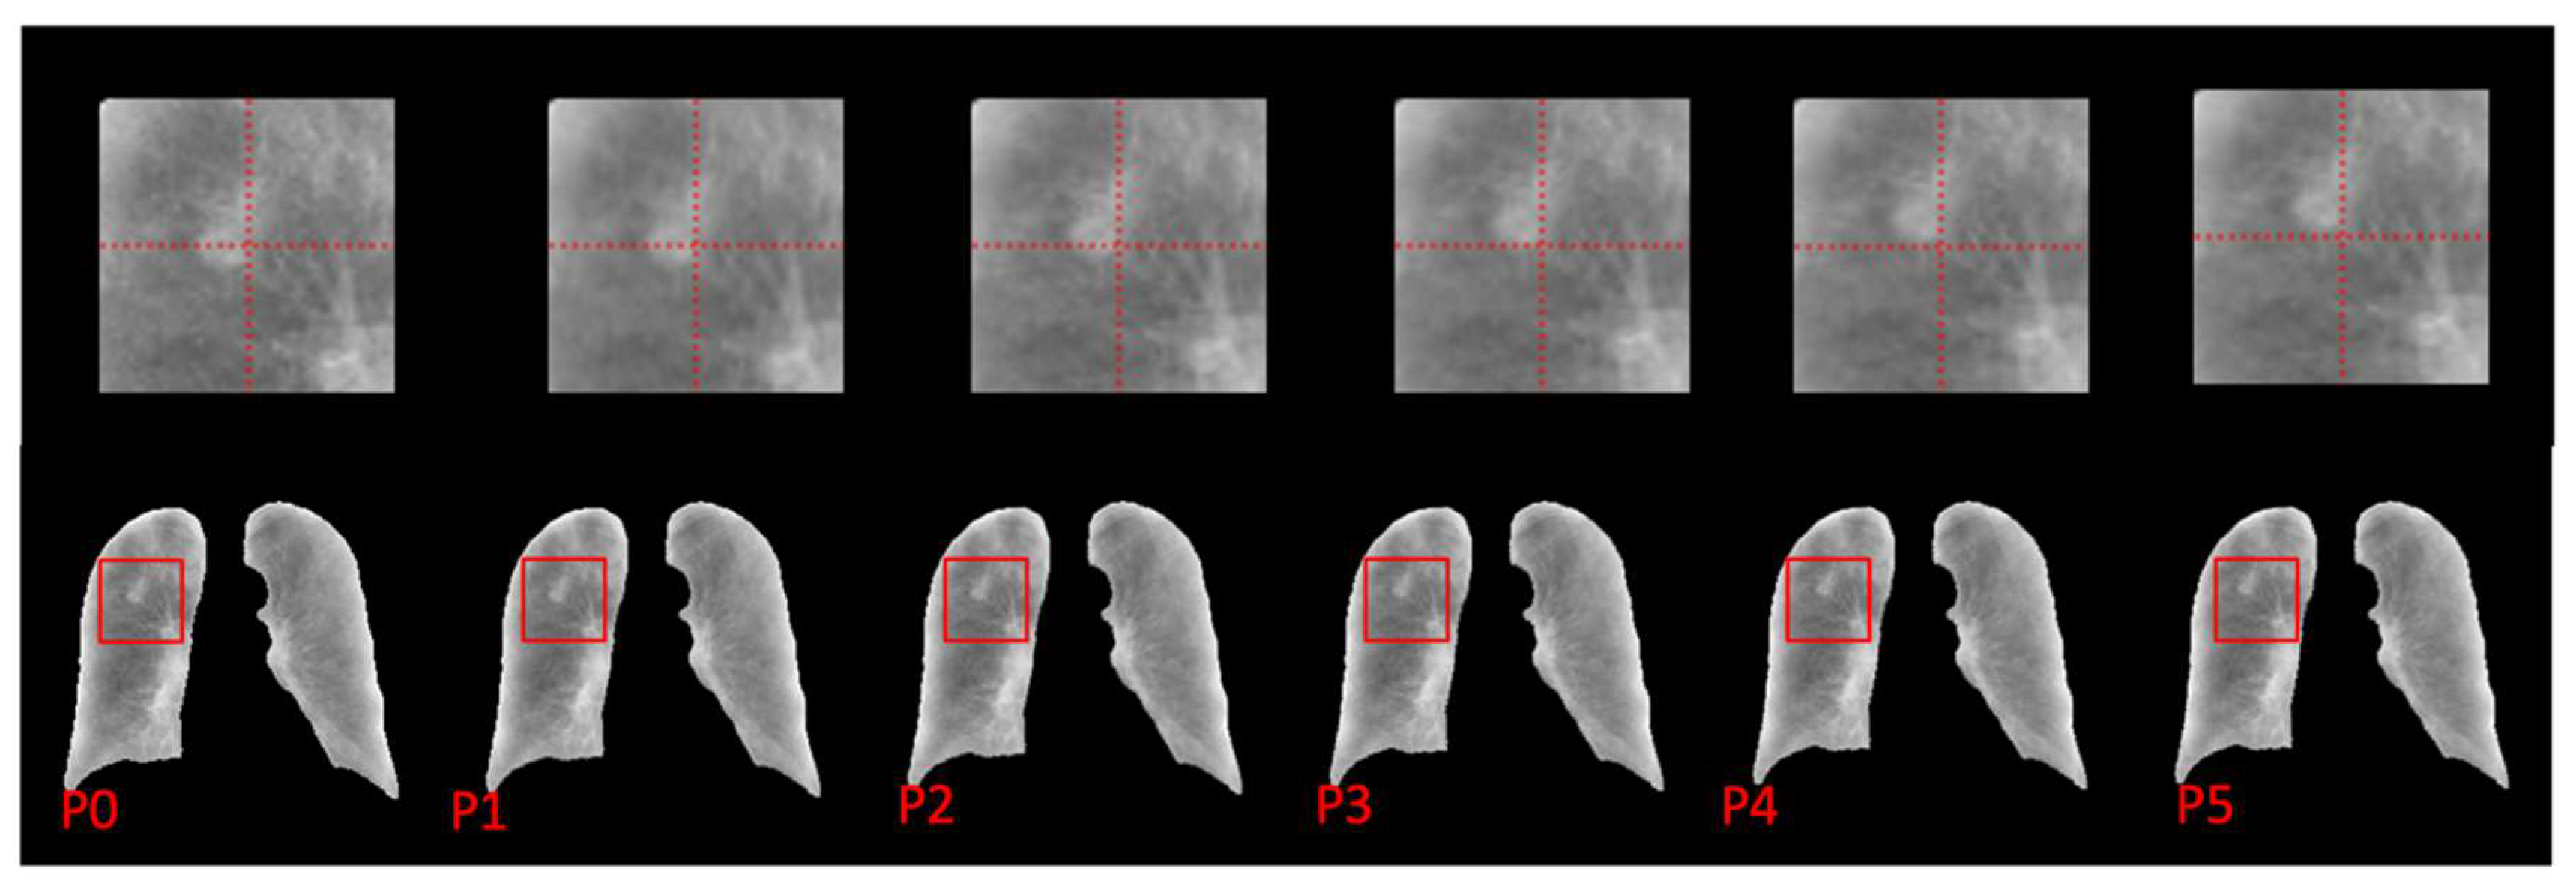

Given the absence of dynamic chest X-ray data, we conducted our network training using digital reconstructed radiograph (DRR) images to establish proof of concept. Subsequently, we sourced chest X-rays from the JSRT dataset [28] for external validation. These chest X-ray images were processed and integrated into the RMS framework for motion synthesis without further training. A representative example of the motion simulation results from one chest X-ray is illustrated in Figure 6. Notably, the relative motion of a nodule in the right upper lobe becomes readily apparent, alerting radiologists to the presence of abnormal lung function in this specific region.

Figure 6.

Simulated phase images of a JSRT chest X-ray sample. The region around the nodule was enlarged to improve the visibility of the relative motion.

The prediction results of one patient randomly selected from the test set are visualized in Figure 3. It can be quantitively observed that the anatomical details of the lung are well-preserved in the subsequent phases. And the diaphragm motion is shown by the distance between the diaphragm dome and the reference line. The lung tissue’s two-dimensional contraction is visualized by calculating the Jacobian determinant. In the process of exhalation, as respiratory gases are gradually expelled from the lungs, a progressive diminution of the lung volume is observed. This progress of contraction was visualized by sequentially plotting the increasing value of the Jacobian determinant. It can also be observed that the Jacobian determinant of the lower lung region is larger than the upper lung region, representing a higher expansion or contraction factor during respiration, which is consistent with pulmonary biomechanics. The distribution appears smooth without significant fluctuations. The simulation results presented in Figure 6 further substantiate the practicality of integrating this technique into clinical workflows, offering radiologists valuable supplementary information to enhance diagnosis.